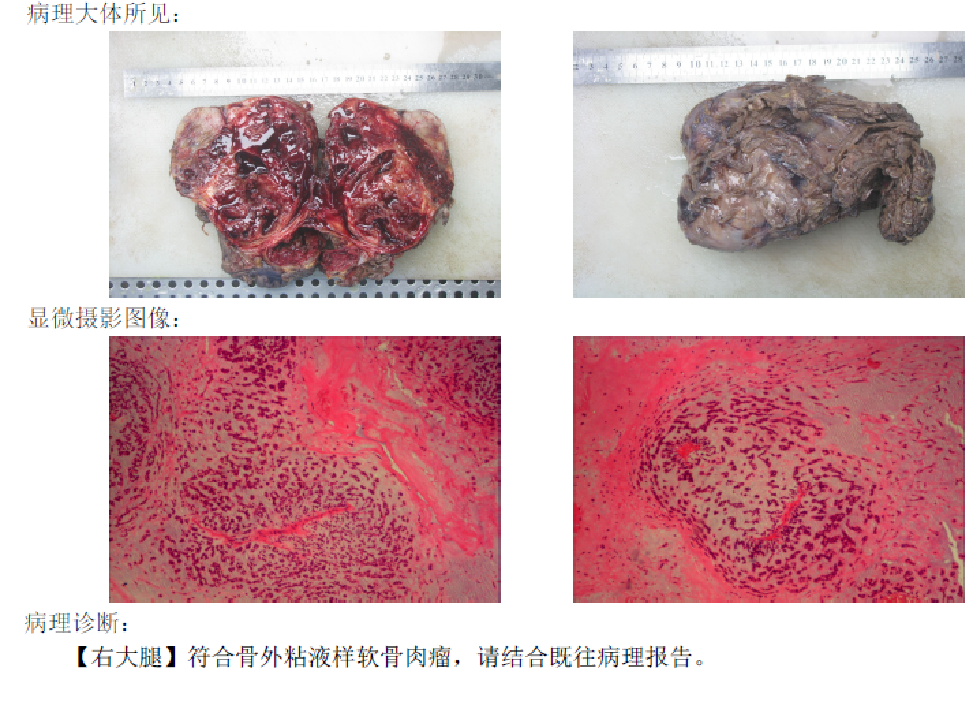

病理诊断:骨外粘液样软骨肉瘤

骨外粘液样软骨肉瘤 ( extraskeletal myxoid chondrosarcoma,EMC) 是一种罕见的低度恶性间充质肿瘤,约占所有软组织肉瘤的 3% ,其特征是组织中含有丰富的粘液样基质。该肿瘤生长缓慢,局部复发率和转移率较高。由于 EMC 十分少见, 临床表现不具有特征性,术前早期诊断困难。该病是一种具有自身特征的肿瘤实体,与典型的软骨肉瘤有不同的临床和组织病理学特征, 最早被报道为低度恶性的肿瘤,据最近的统计数据 显示,EMC 患者有较高的局部复发、转移率和死亡率,因此被归类为中度恶性肿瘤。该病的好发年龄为 50 岁,男女比例为 2: 1,最常见的发病部位是四肢深部软组织,尤其是大腿,其他部位如颈部、 足部、眼眶和会阴也有报道。